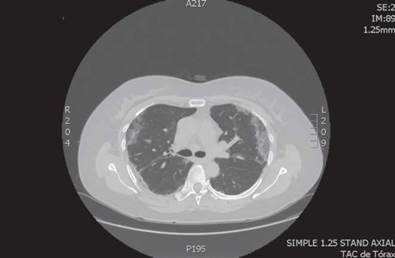

Se realizó ecografía de abdomen total que reportó hemangioma hepático, quiste simple hepático y quiste simple en riñón derecho y TAC de tórax que evidenció patrón en vidrio esmerilado subpleural en ambos pulmones y con predominio en lóbulos inferiores, así como opacidades lineales (Figura 2). Los exámenes de laboratorio realizados se reportan en la Tabla 2.

Fuente: Documento obtenido durante la realización del estudio.

Figura 2 Tomografía axial computarizada de tórax, caso 2.